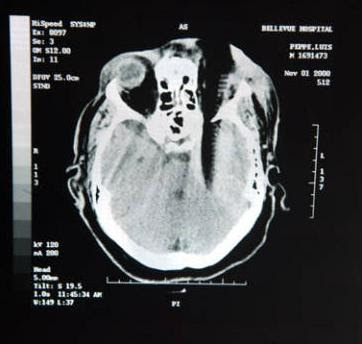

12. Sisir adalah pembunuh.

X-ray Louis Pepe, ketika dia ditikam oleh sisir dalam tengkorak, pada tahun 2000. Ia kehilangan mata kiri dan mata kanannya yang terkena juga. Sisir menyebabkan dia banyak kerusakan: melumpuhkan lengan kanan dan kaki dan kemampuannya untuk berbicara. Penyerang dijatuhi hukuman 23 tahun penjara, gak adil ya gan?